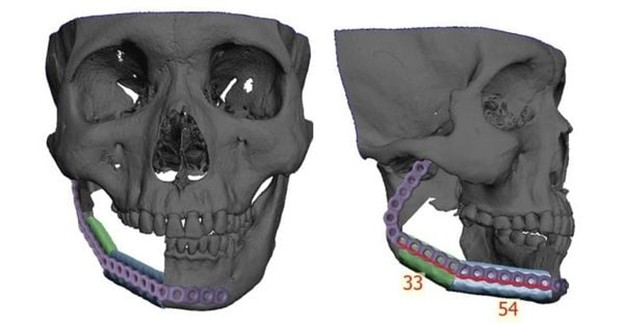

Việc ứng dụng công nghệ tái tạo 3D là một bước tiến rất quan trọng cho phép xác định phẫu thuật một cách chính xác khi cắt các khối u xương hàm dựa trên mô hình 3D đã in sẵn. Bên cạnh đó người bệnh cũng được tái tạo 3D vùng xương cẳng chân nơi lấy xương mác để xác định chính xác các vị trí cắt xương tạo góc làm sao cho phù hợp với các đoạn cong của xương hàm dưới giống như thật để thay thế xương hàm dưới vừa bị cắt do khối u.

Tại Bệnh viện Nhân dân 115, bên cạnh sự phát triển mạnh trong lĩnh vực Vi phẫu, Tạo hình và Chỉnh hình, chúng tôi áp dụng thêm công nghệ kỹ thuật số 3D trong thiết kế “Template” và lập kế hoạch phẫu thuật giúp đơn giản hóa và tối ưu hóa điều trị, tăng độ chính xác, giảm thời gian phẫu thuật và cải thiện kết quả tái tạo cấu trúc xương hàm dưới.

Người bệnh được lên chương trình phẫu thuật cắt đoạn khối u xương hàm dưới với lề cắt an toàn 1cm, đồng thời xương hàm dưới được tái tạo bằng vạt xương mác tự do. Đây là một kỹ thuật phức tạp, yêu cầu kinh nghiệm, sự điêu luyện, tỉ mỉ và sức bền từ ekip phẫu thuật. Tuy nhiên, nhờ sự hỗ trợ bởi công nghệ 3D, giúp các bác sĩ mô phỏng trước từng thao tác cắt, ghép và tái tạo nên ca phẫu thuật diễn ra rất chính xác và nhanh chóng.

Để tối ưu hóa kết quả điều trị, chúng tôi thiết kể mô hình giả lập trên phần mềm 3D dựa theo CT-Scan của người bệnh, giúp mô phỏng vị trí cắt đoạn xương hàm dưới và kế hoạch tái tạo bằng xương mác. Công nghệ này cho phép thiết kế chính xác máng cắt xương và hình dáng nẹp tái tạo, tạo mẫu hàm và máng hướng dẫn phẫu thuật với độ chính xác cao, an toàn.